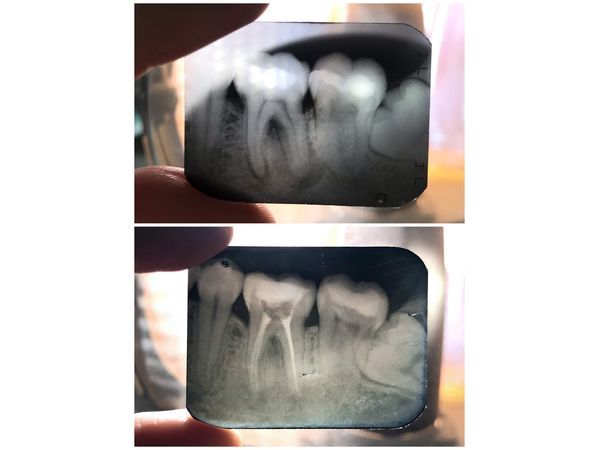

Внутриротовая рентгенограмма зуба обнаружила:

- очаг затемнения с ровными контурами (тень пломбы) на жевательной поверхности зуба;

- уменьшение полости зуба;

- прямые корни;

- свободные корневые каналы;

- снижение плотности кости вокруг верхушек медиальных (ближних) корней зуба — округлый очаг с нечёткими границами размером 1,5×3 мм;

- очаг снижения плотности кости округлой формы с чёткими границами вдоль всей длины дистального (дальнего) корня — апико-латеральная киста размером примерно 14×7 мм;

- снижение плотности кости в месте расхождения корней;

- нечёткий костный рисунок альвеолы (зубной лунки).

Спустя полгода она не предъявляла никаких жалоб. По результатам рентгенологического контроля, костные ткани начали восстанавливаться, просветления исчезли.